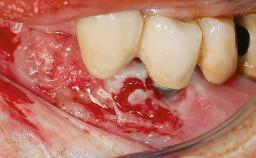

Retreatment of a Patient with Multiple Biological and Technical Complications and Failures

A 66-year-old patient presented because of retention loss of the tooth-supported FDP in the right maxilla (x-13-x-11). The mandibular full-arch implant-supported reconstruction (x-i34-i33-x-x-x-x-i43-i44-x) had suffered extreme wear. His medical history revealed high blood pressure, controlled with anti-hypertensive medication. The patient was a light smoker (2 to 3 cigarettes per day). The existing reconstructions had been performed alio loco about five years previously. That treatment had taken an extensive amount of time, and as early as during the fabrication of the reconstructions, multiple complications had occurred with the provisionals.